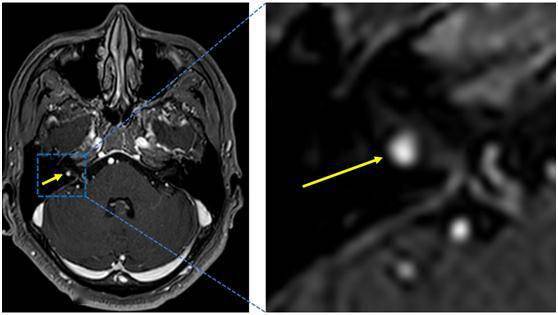

患者以面肌痉挛收治入院 , 没想到在完善相关检查的时候 , 医生发现了新的问题 。 张勇介绍 , “检查结果显示 , 宋先生的腰1椎体有新鲜的骨折 , 头颅MRA发现了一个仅3mm的听神经瘤 , 就像‘绿豆’一样的大小 。 ”

术前颅脑MRI(黄色箭头显示为听神经瘤) 。 通讯员供图